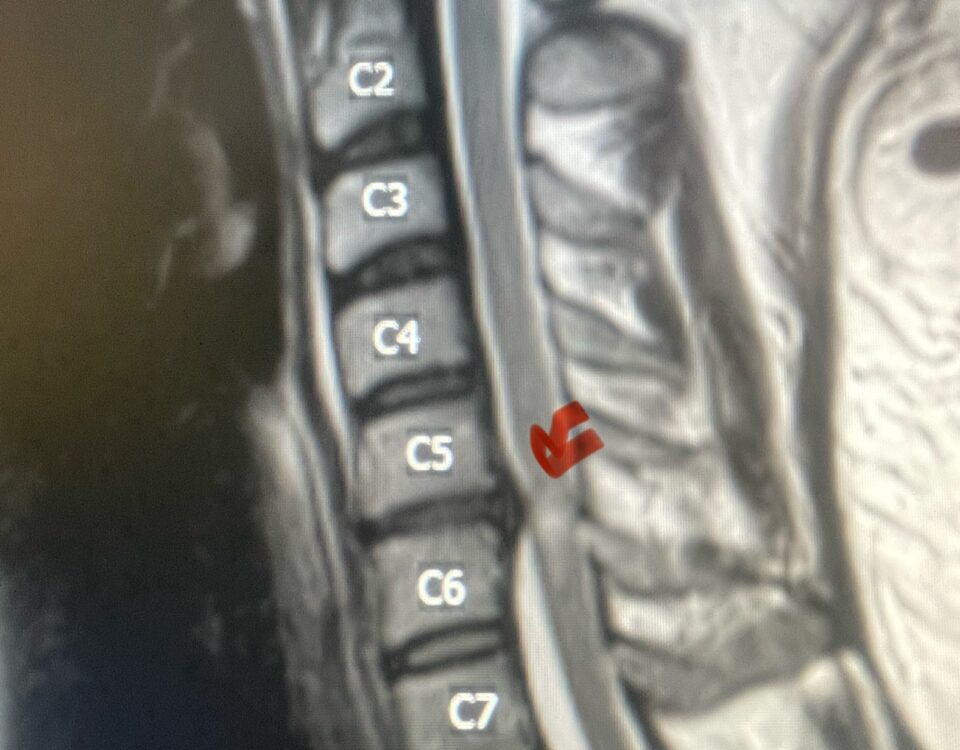

Here is a tough case: This is a 72 year-old male who presented with several months of progressive neck pain without symptoms of the arms or legs. […]